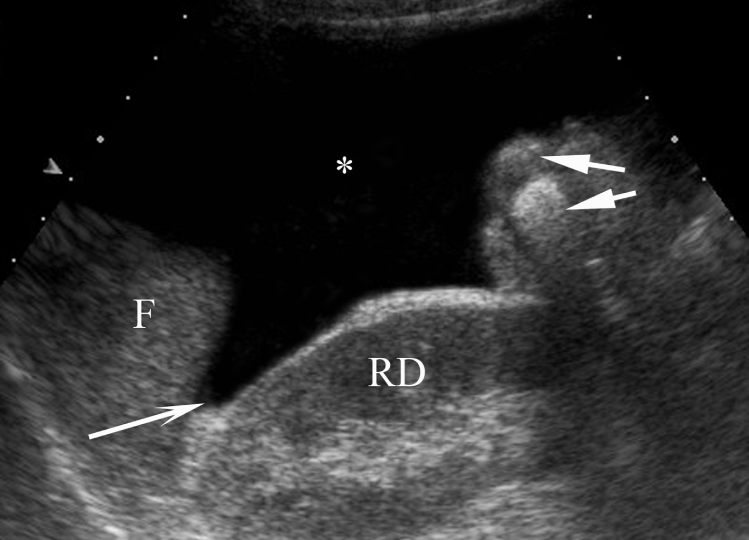

En échographie, il s’agit d’un épanchement liquidien anéchogène (figure 4.1).

Fig. 4.1 Coupe échographique sagittale paramédiane droite d’une ascite abondante (∗).

Le patient est en décubitus dorsal et l’ascite occupe la partie la plus déclive du péritoine [le récessus hépato-rénal de Morison (flèche longue) situé entre la face inférieure du foie (F) et la face antérieure du rein droit (RD)]. On observe également des anses digestives contenant du gaz (flèches courtes).

Source : CERF, CNEBMN, 2022.